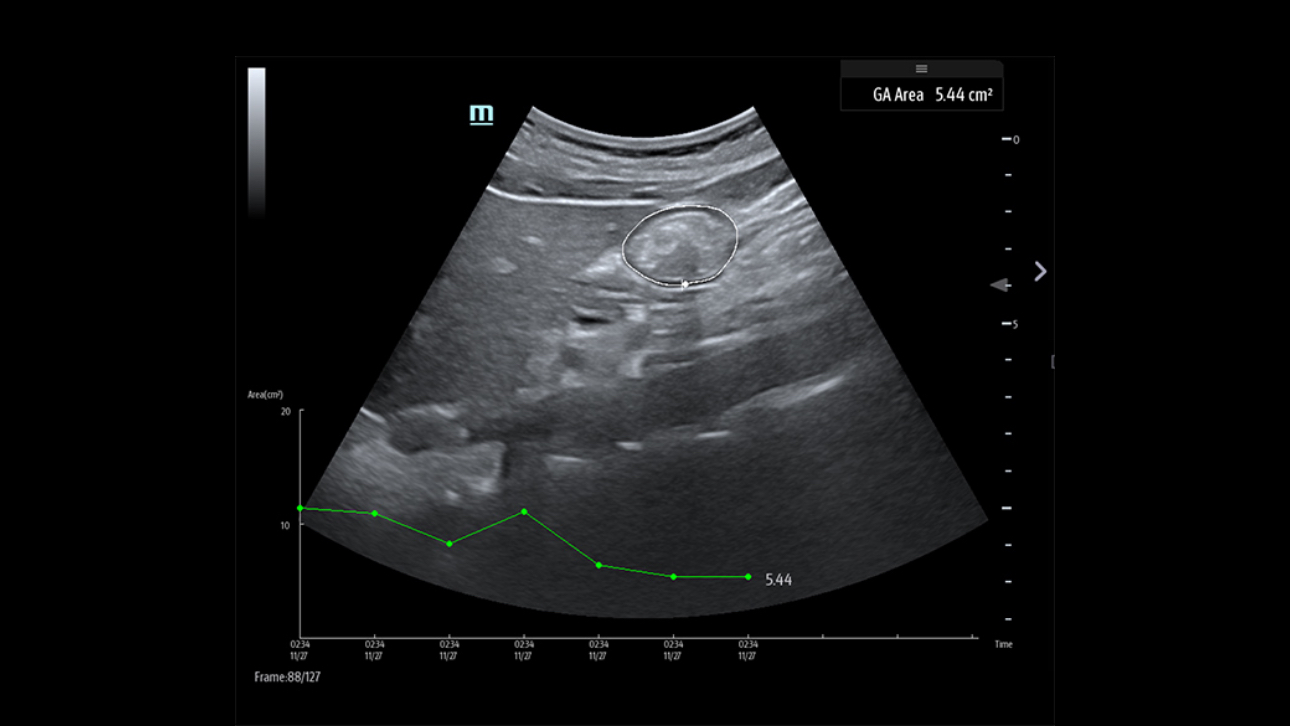

El sistema de ultrasonido TE9 estĂĄ dise?ado para ayudar a facilitar una mejor atenciĂłn al paciente y ampliar las capacidades de imagen para aplicaciones de anestesia, emergencias y cuidados crĂticos. Con funciones avanzadas, una gran pantalla tĂĄctil y una tecnologĂa de imagen superior, el TE9 es ideal para ayudar a mejorar la eficiencia clĂnica y la confianza en el diagnĂłstico. Las herramientas de automatizaciĂłn inteligentes brindan mediciones rĂĄpidas y reproducibles para exĂĄmenes y procedimientos fiables, incluso en entornos de gran presiĂłn.